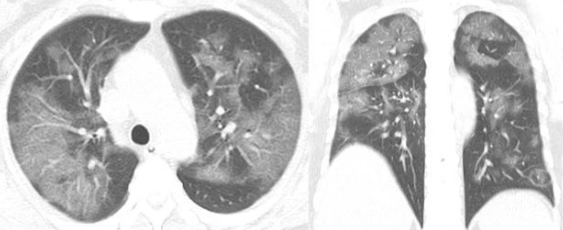

Trong hình ảnh chụp X-quang của bệnh nhân được Hiệp hội X-quang Bắc Mỹ công bố, có thể thấy các đốm trắng xuất hiện ở góc dưới lá phổi, thường được biết đến như tổn thương kính mờ (GGO). Khi so sánh ảnh theo thứ tự từ A đến F, hiện tượng khoảng không khí trong phổi bị dịch thay thế càng rõ ràng hơn.

Ảnh X-quang của bệnh nhân nam 44 tuổi được sắp xếp theo thứ tự thời gian.